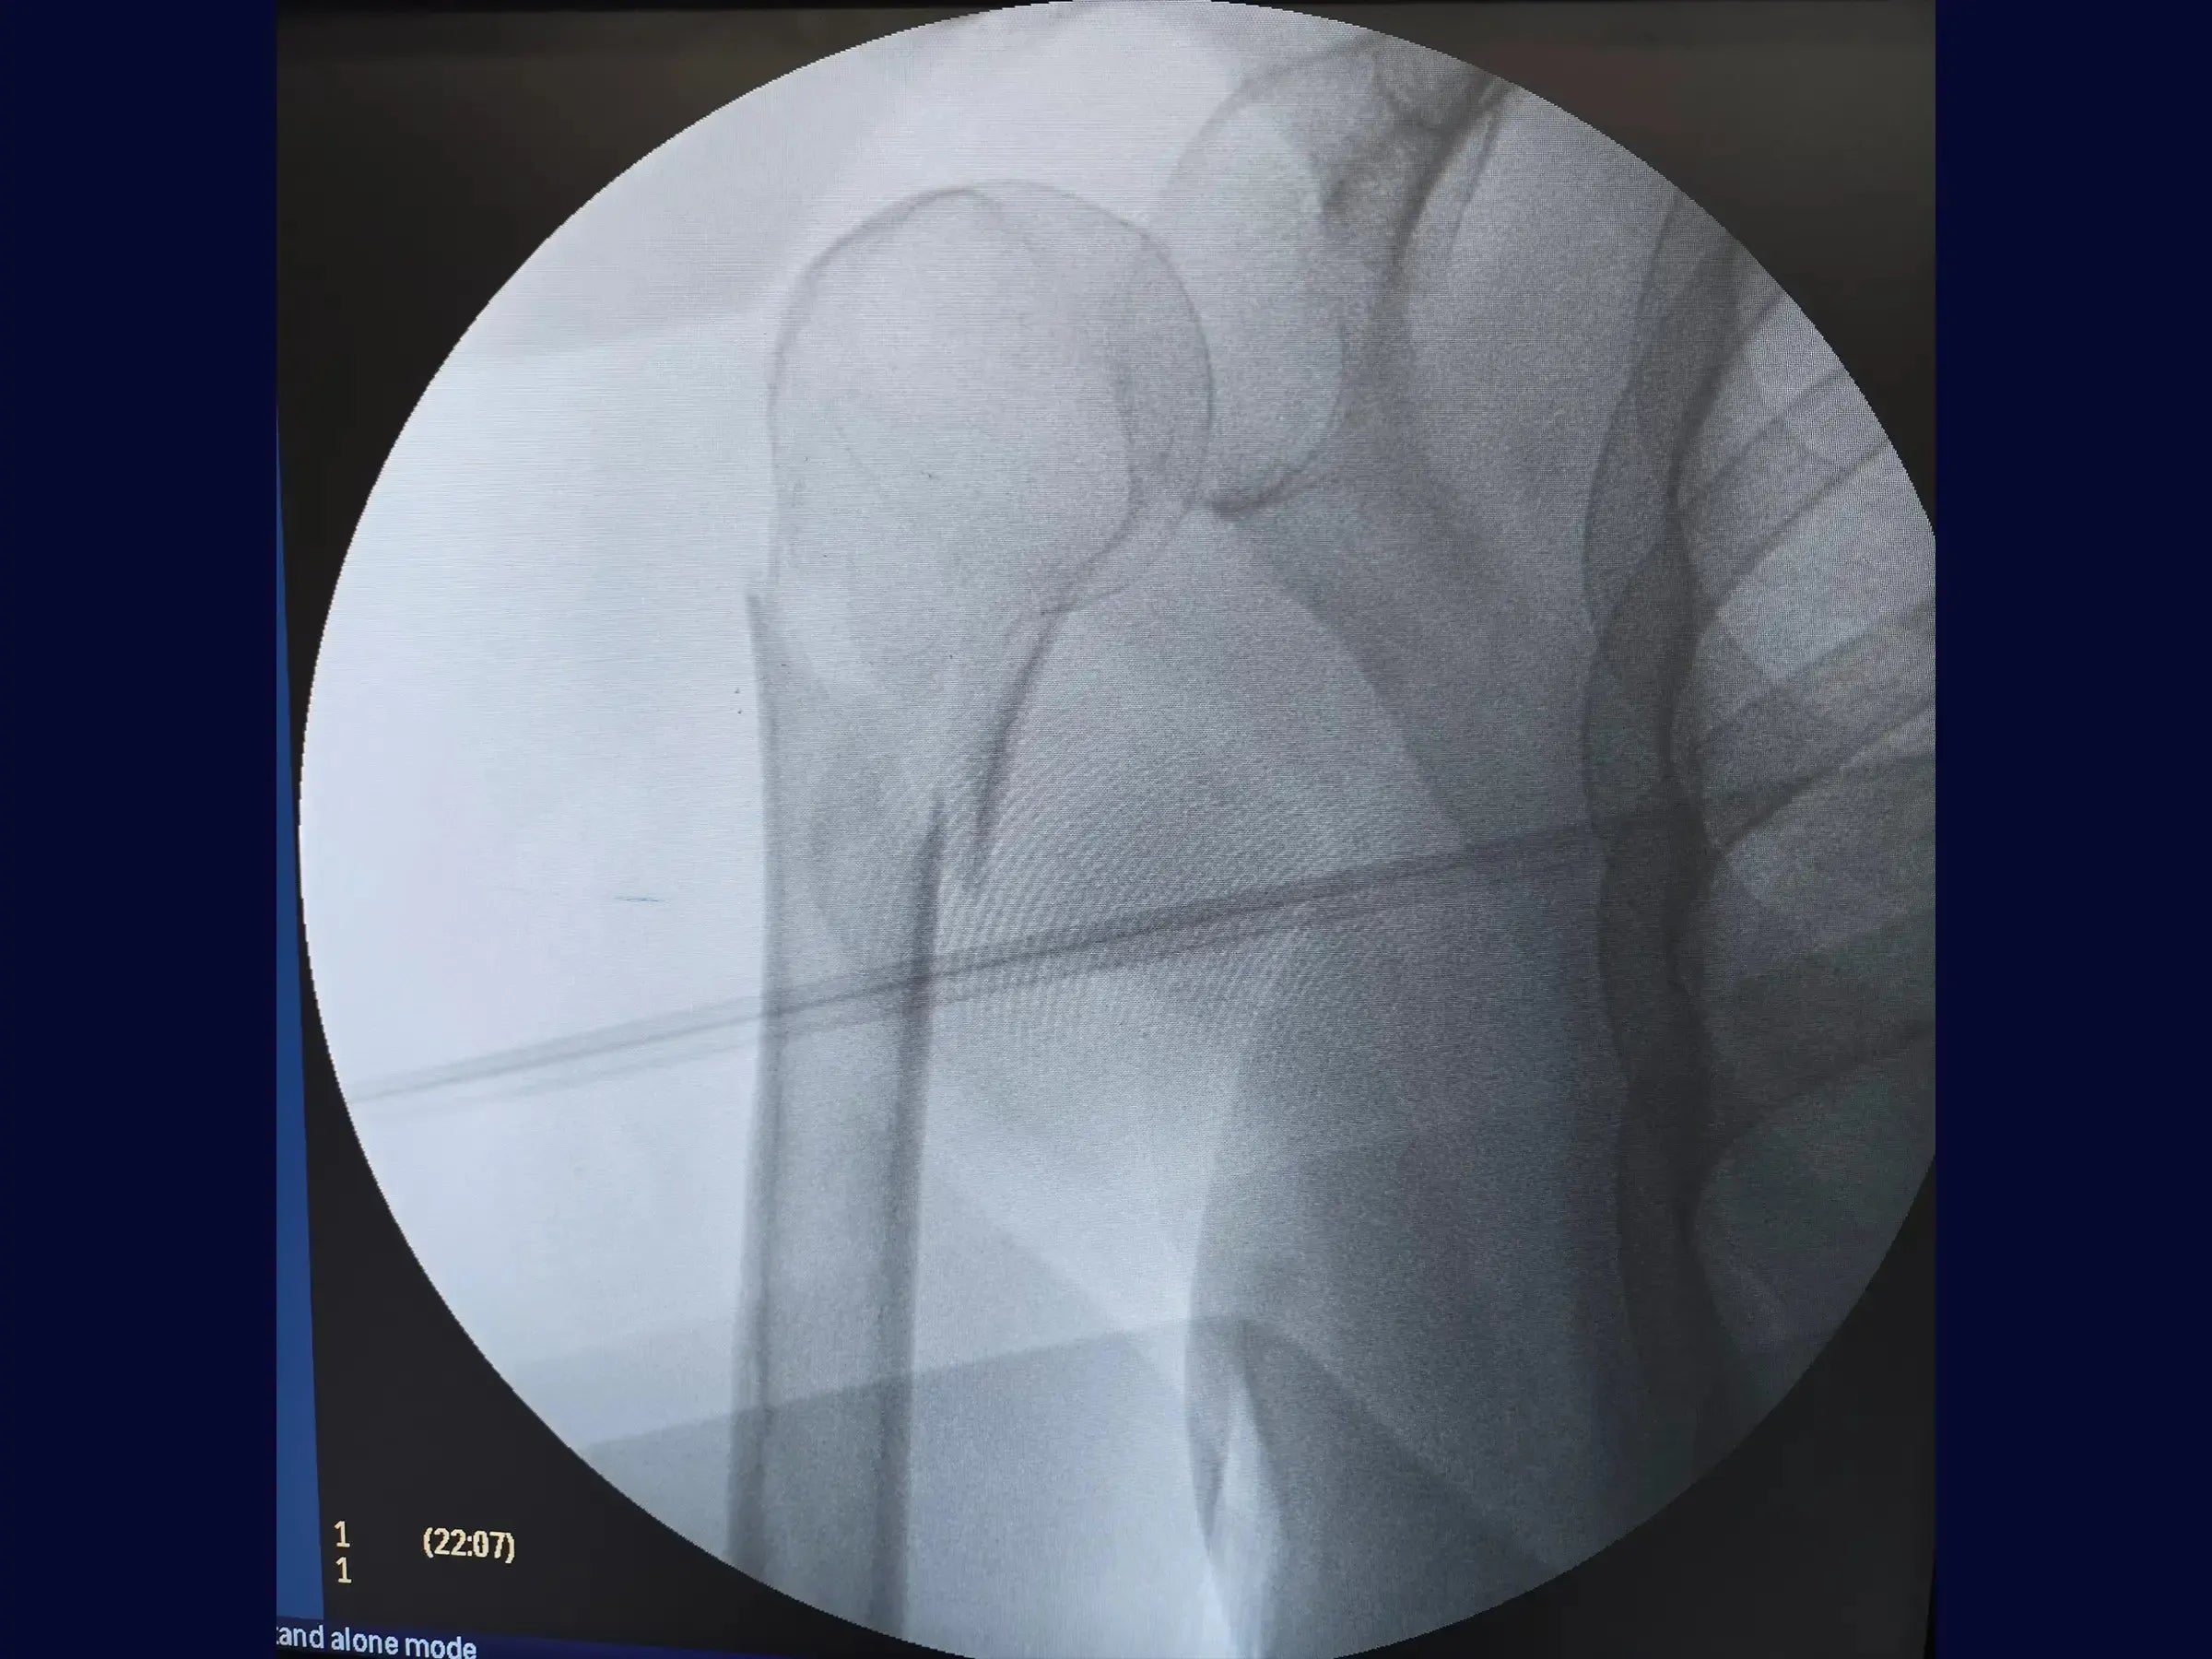

- Precise Guide Wire Management: Methodology to valgus the varus proximal fragment and optimize the entry angle of the intramedullary nail guide wire.

- Enhanced Radiographic Control: Orientation techniques in anteroposterior and lateral views for precise insertion of the wire and rod.